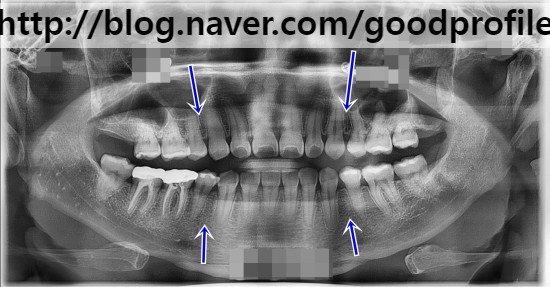

[ASOを受けた後、青い矢印部分の

歯がなくなりました]

上の写真を見ると

ASOをした跡が見えます。

青色の矢印が

癒合部位を示しています。

*****今日のレントゲンは

ASOの後にまた

顔面輪郭を再確認した結果で

私の説明と若干の差がある

可能性があります。*****